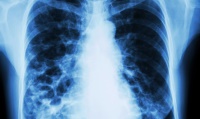

Bronchiectasis is a chronic lung disease marked by permanent airway dilation, mucus accumulation, recurrent infections, and persistent inflammation. Affecting approximately 1 million individuals worldwide, the disease is associated with COPD, cystic fibrosis, severe respiratory infections, or congenital disorders. Patients experience chronic cough, sputum production, fatigue, and progressive lung function decline, impacting overall quality of life. Rising awareness and improved diagnostics have increased the demand for targeted therapies in bronchiectasis management.